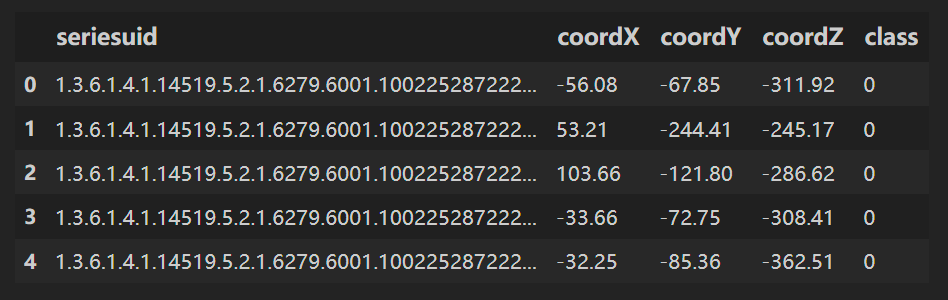

用 pandas 读取 candidates.csv;

candidates.csv⽂件中的LUNA标注包含了CT序列、候选结节的位置,以及⼀个标识(指示该候选者是否真的是结节)

df = pd.read_csv(path+'candidates.csv')

df.head()